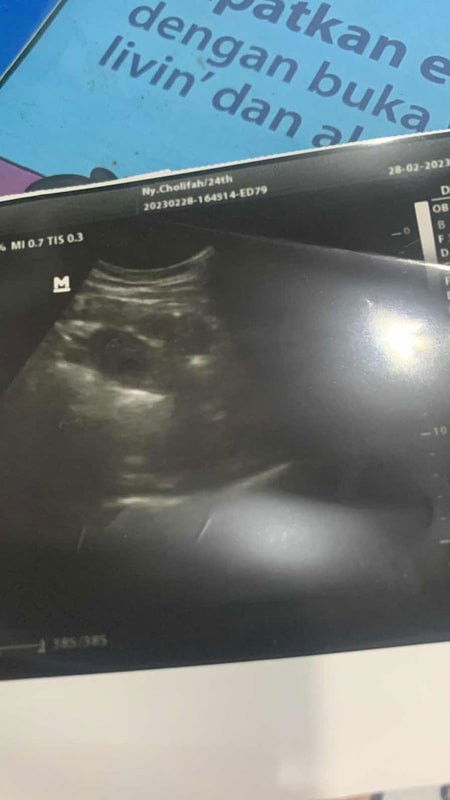

Usg ini menurut bunda 1 atau 2 kantong

Ini ada berapa kantong ya bun

Bun mau minta pendapat dong ini 2 atau 1 kantong yaaa .. soalnya awal dilihat dokter bilang 2 tp belum tentu#ingintahu ##pleasehelp